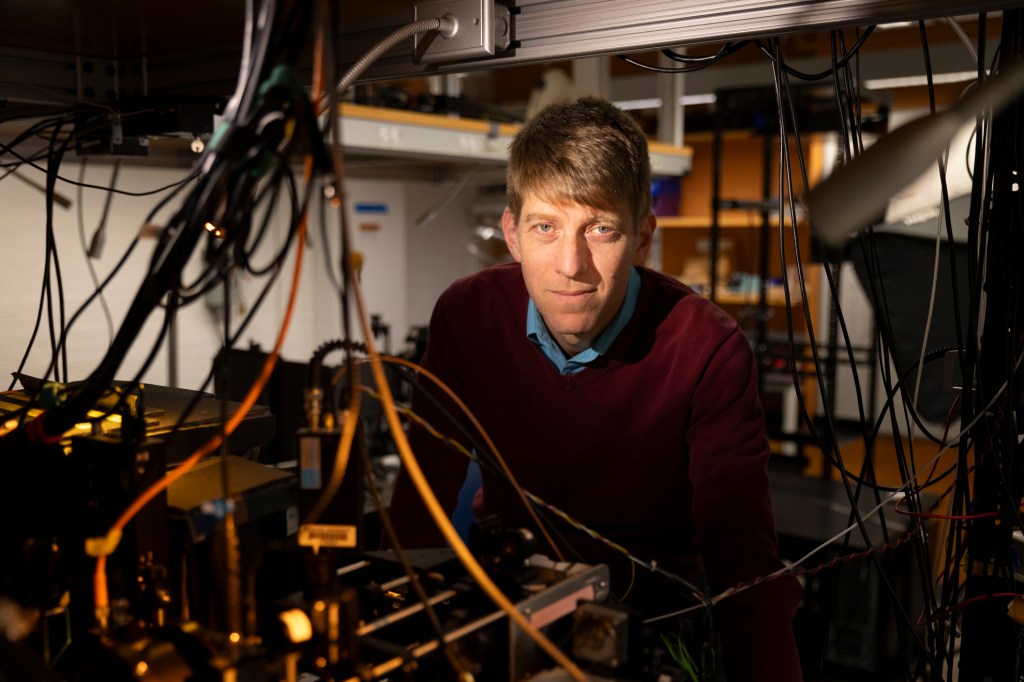

Tracking precisely how learning, memories are formed

Groundbreaking new technique may offer insights for new therapies to treat disorders like dementia